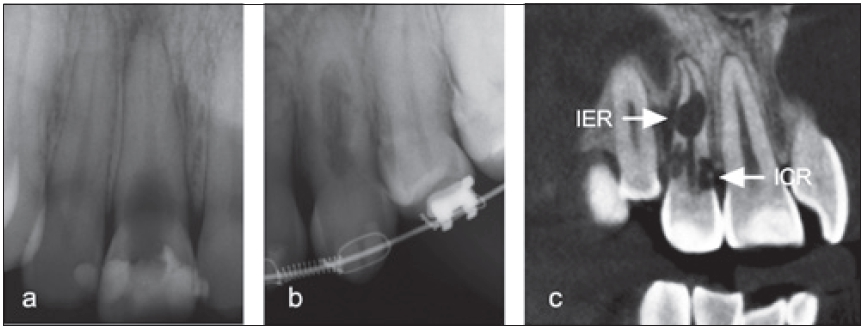

Ist die externe Resorption nicht zugängig (z.B. im Approximalraum) und kann selbst mit chirurgischen Mitteln nicht erreicht werden, sollte man versuchen, sie über den orthograden endodontischen Weg zu verschließen [32]. Analog dazu müssen die Defekte interner Resorptionen nach Entfernung des Resorptionsgewebes gefüllt und Kommunikationen zur Wurzeloberfläche mit hydraulischen Kalziumsilikatzementen verschlossen werden (Abb. 16).

Dr. Widbiller